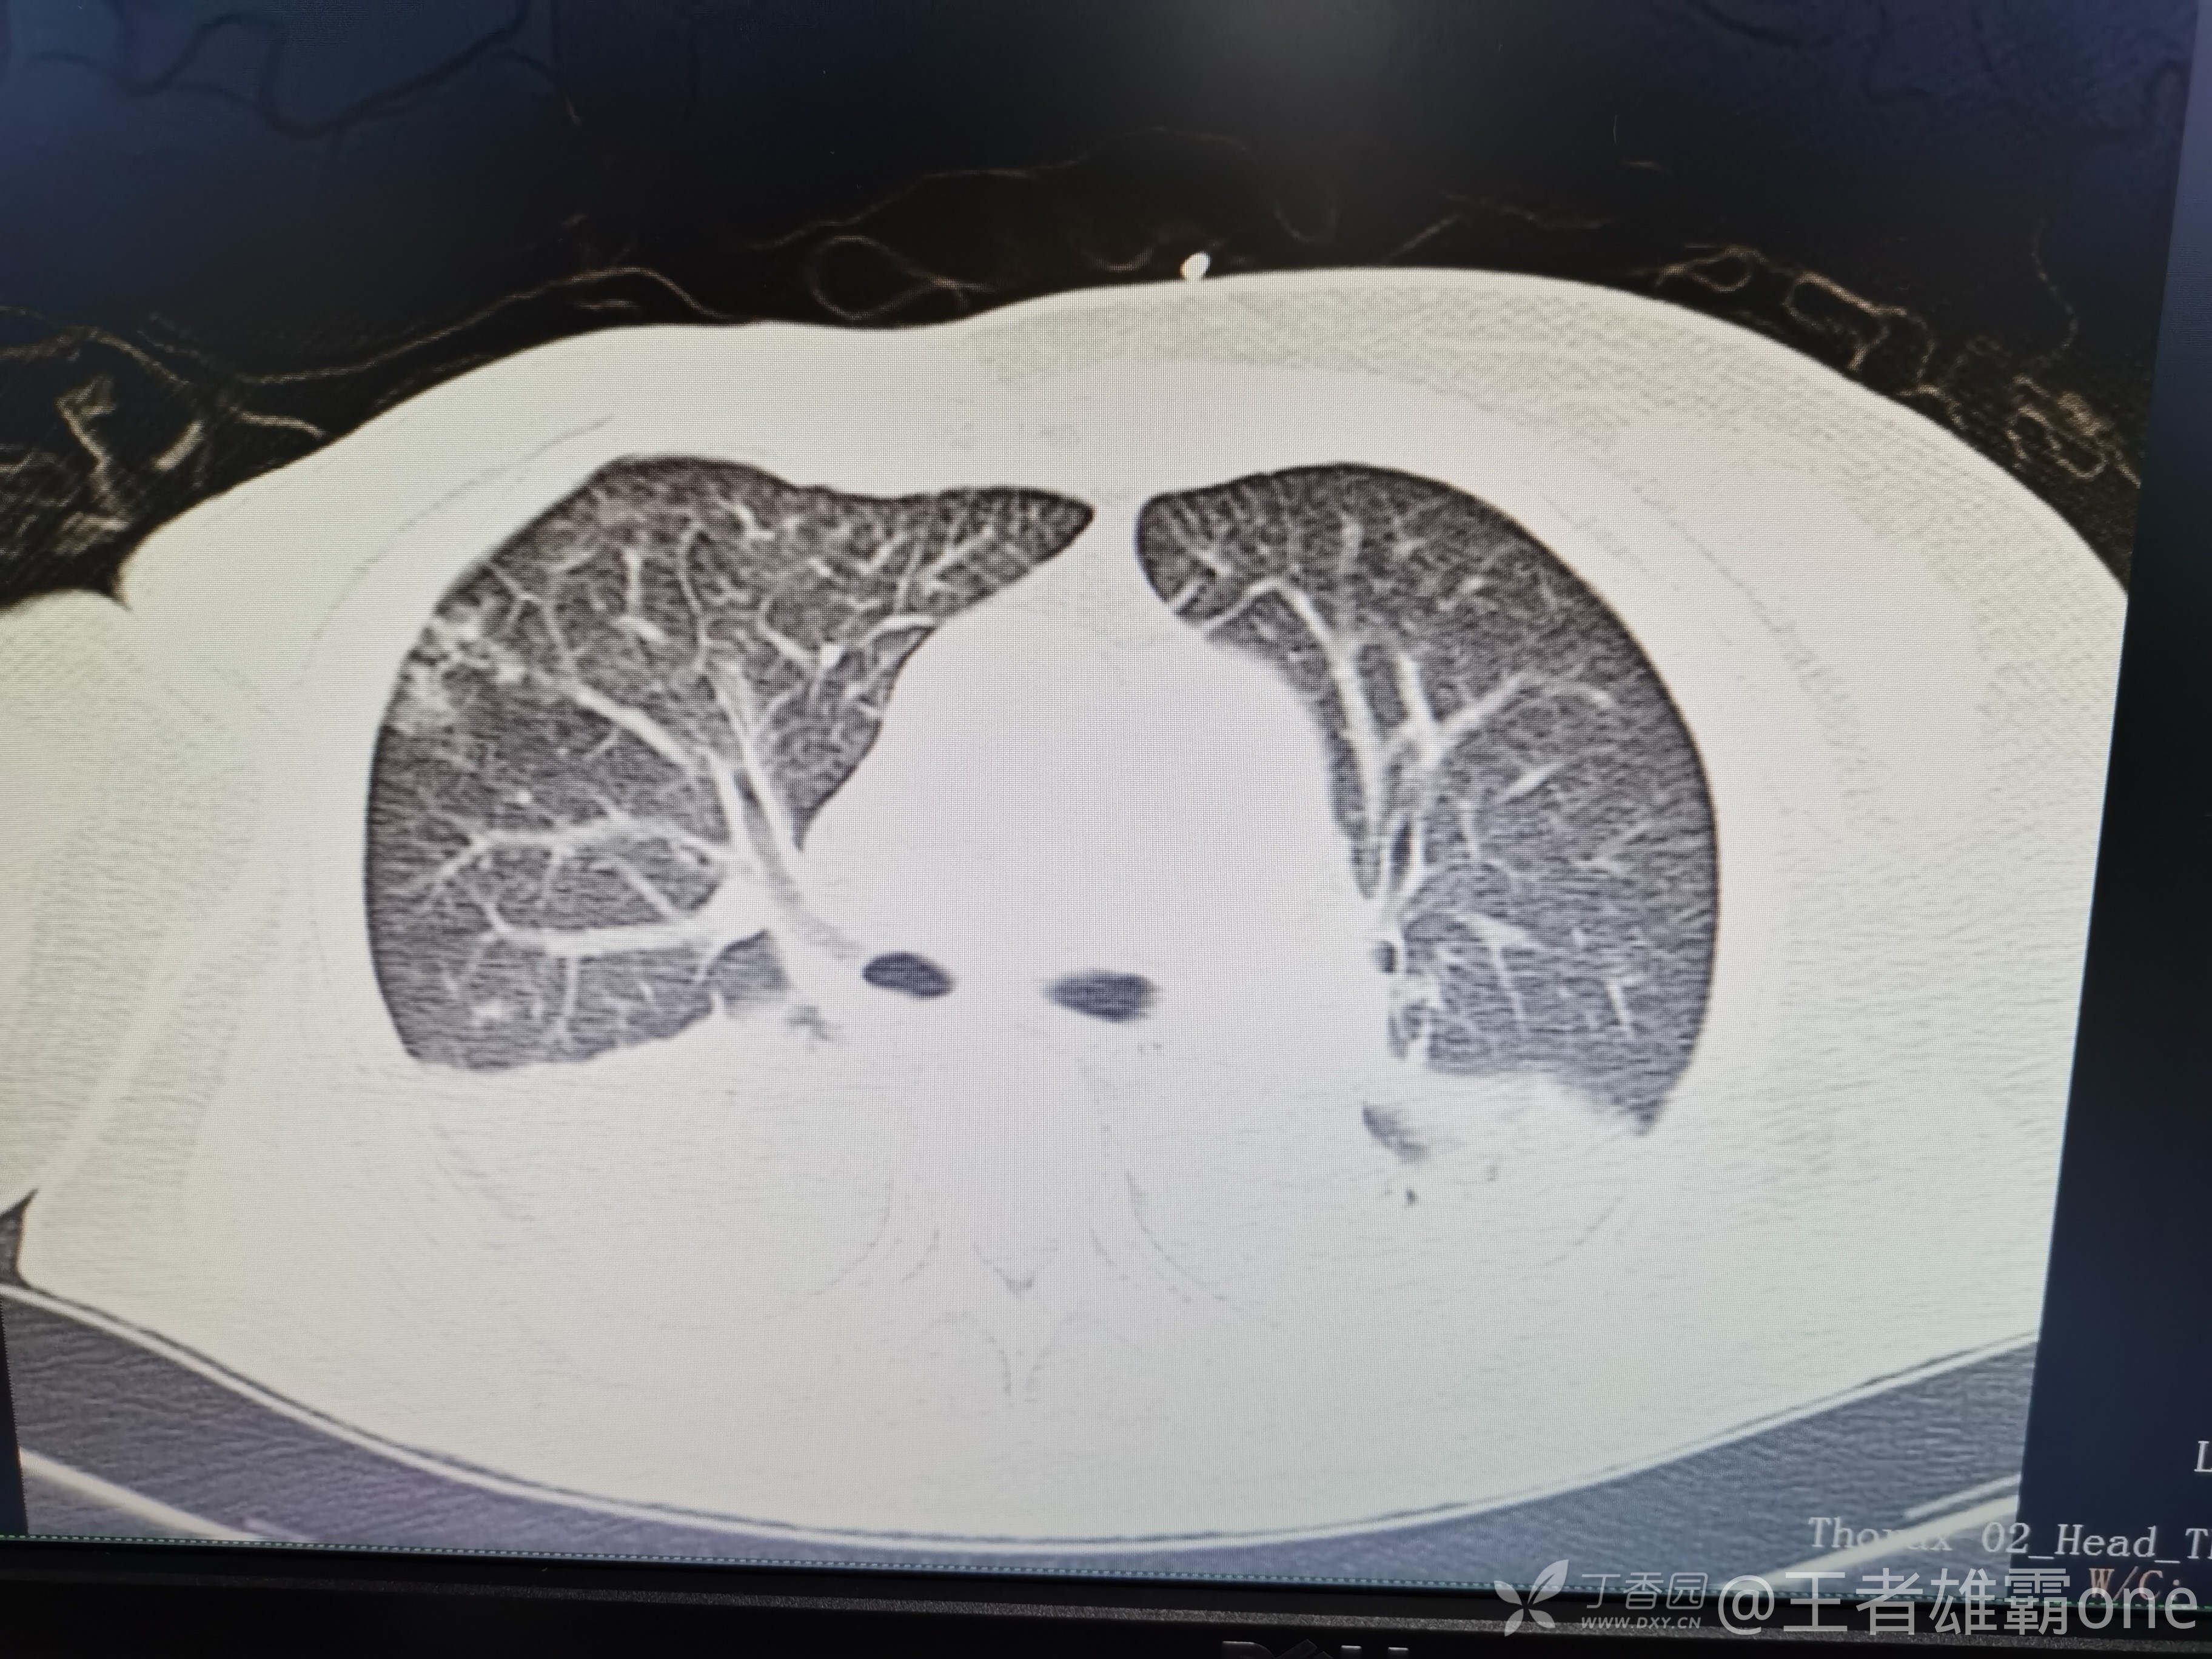

早上复查血常规:血红蛋白100g/L,白细胞11.1×109/L,血小板29×109/L。凝血功能:APTT37.9s,纤维蛋白原3.01g/L,凝血酶时间18.6s,D二聚体21530ug/L。生化:白蛋白36.2g/L,胆红素指标正常,谷丙56U/L,总胆红素38mmol/L,直接胆红素12.1mmol/L,谷草57U/L,肌酐91.1ummol/L,尿素13.97mmol/L,超敏C反应蛋白142.1mg/L。降钙素原17.70ng/ml。脑钠肽前体2164pg/ml。复查胸部CT:

那么问题来了,出现呼吸衰竭气管插管的病因是?请大家讨论分析!